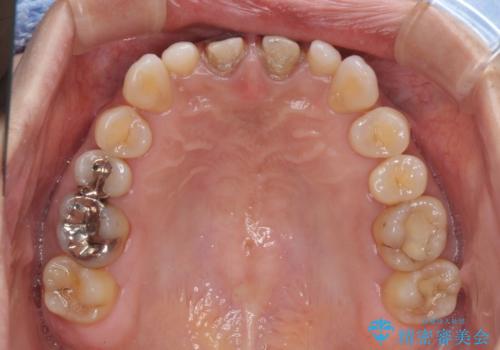

- 他院で奥歯に虫歯があると言われて、ご来院された患者様です。チェックしたところ、奥歯に虫歯は認められませんでした。

前歯に違和感や根尖病巣(根の先に細菌が溜まっている)が認められたため、治療をご提案しました。

セラミック治療と根管治療を行いました。

患者様は、もともと奥歯の虫歯を心配してご来院されましたが、前歯に問題が見つかりました。

金属を使用したメタルボンドクラウンが入っていたため、いつかオールセラミックにしたいときに根管治療も行ったほうが良いとご提案し、今回行いました。